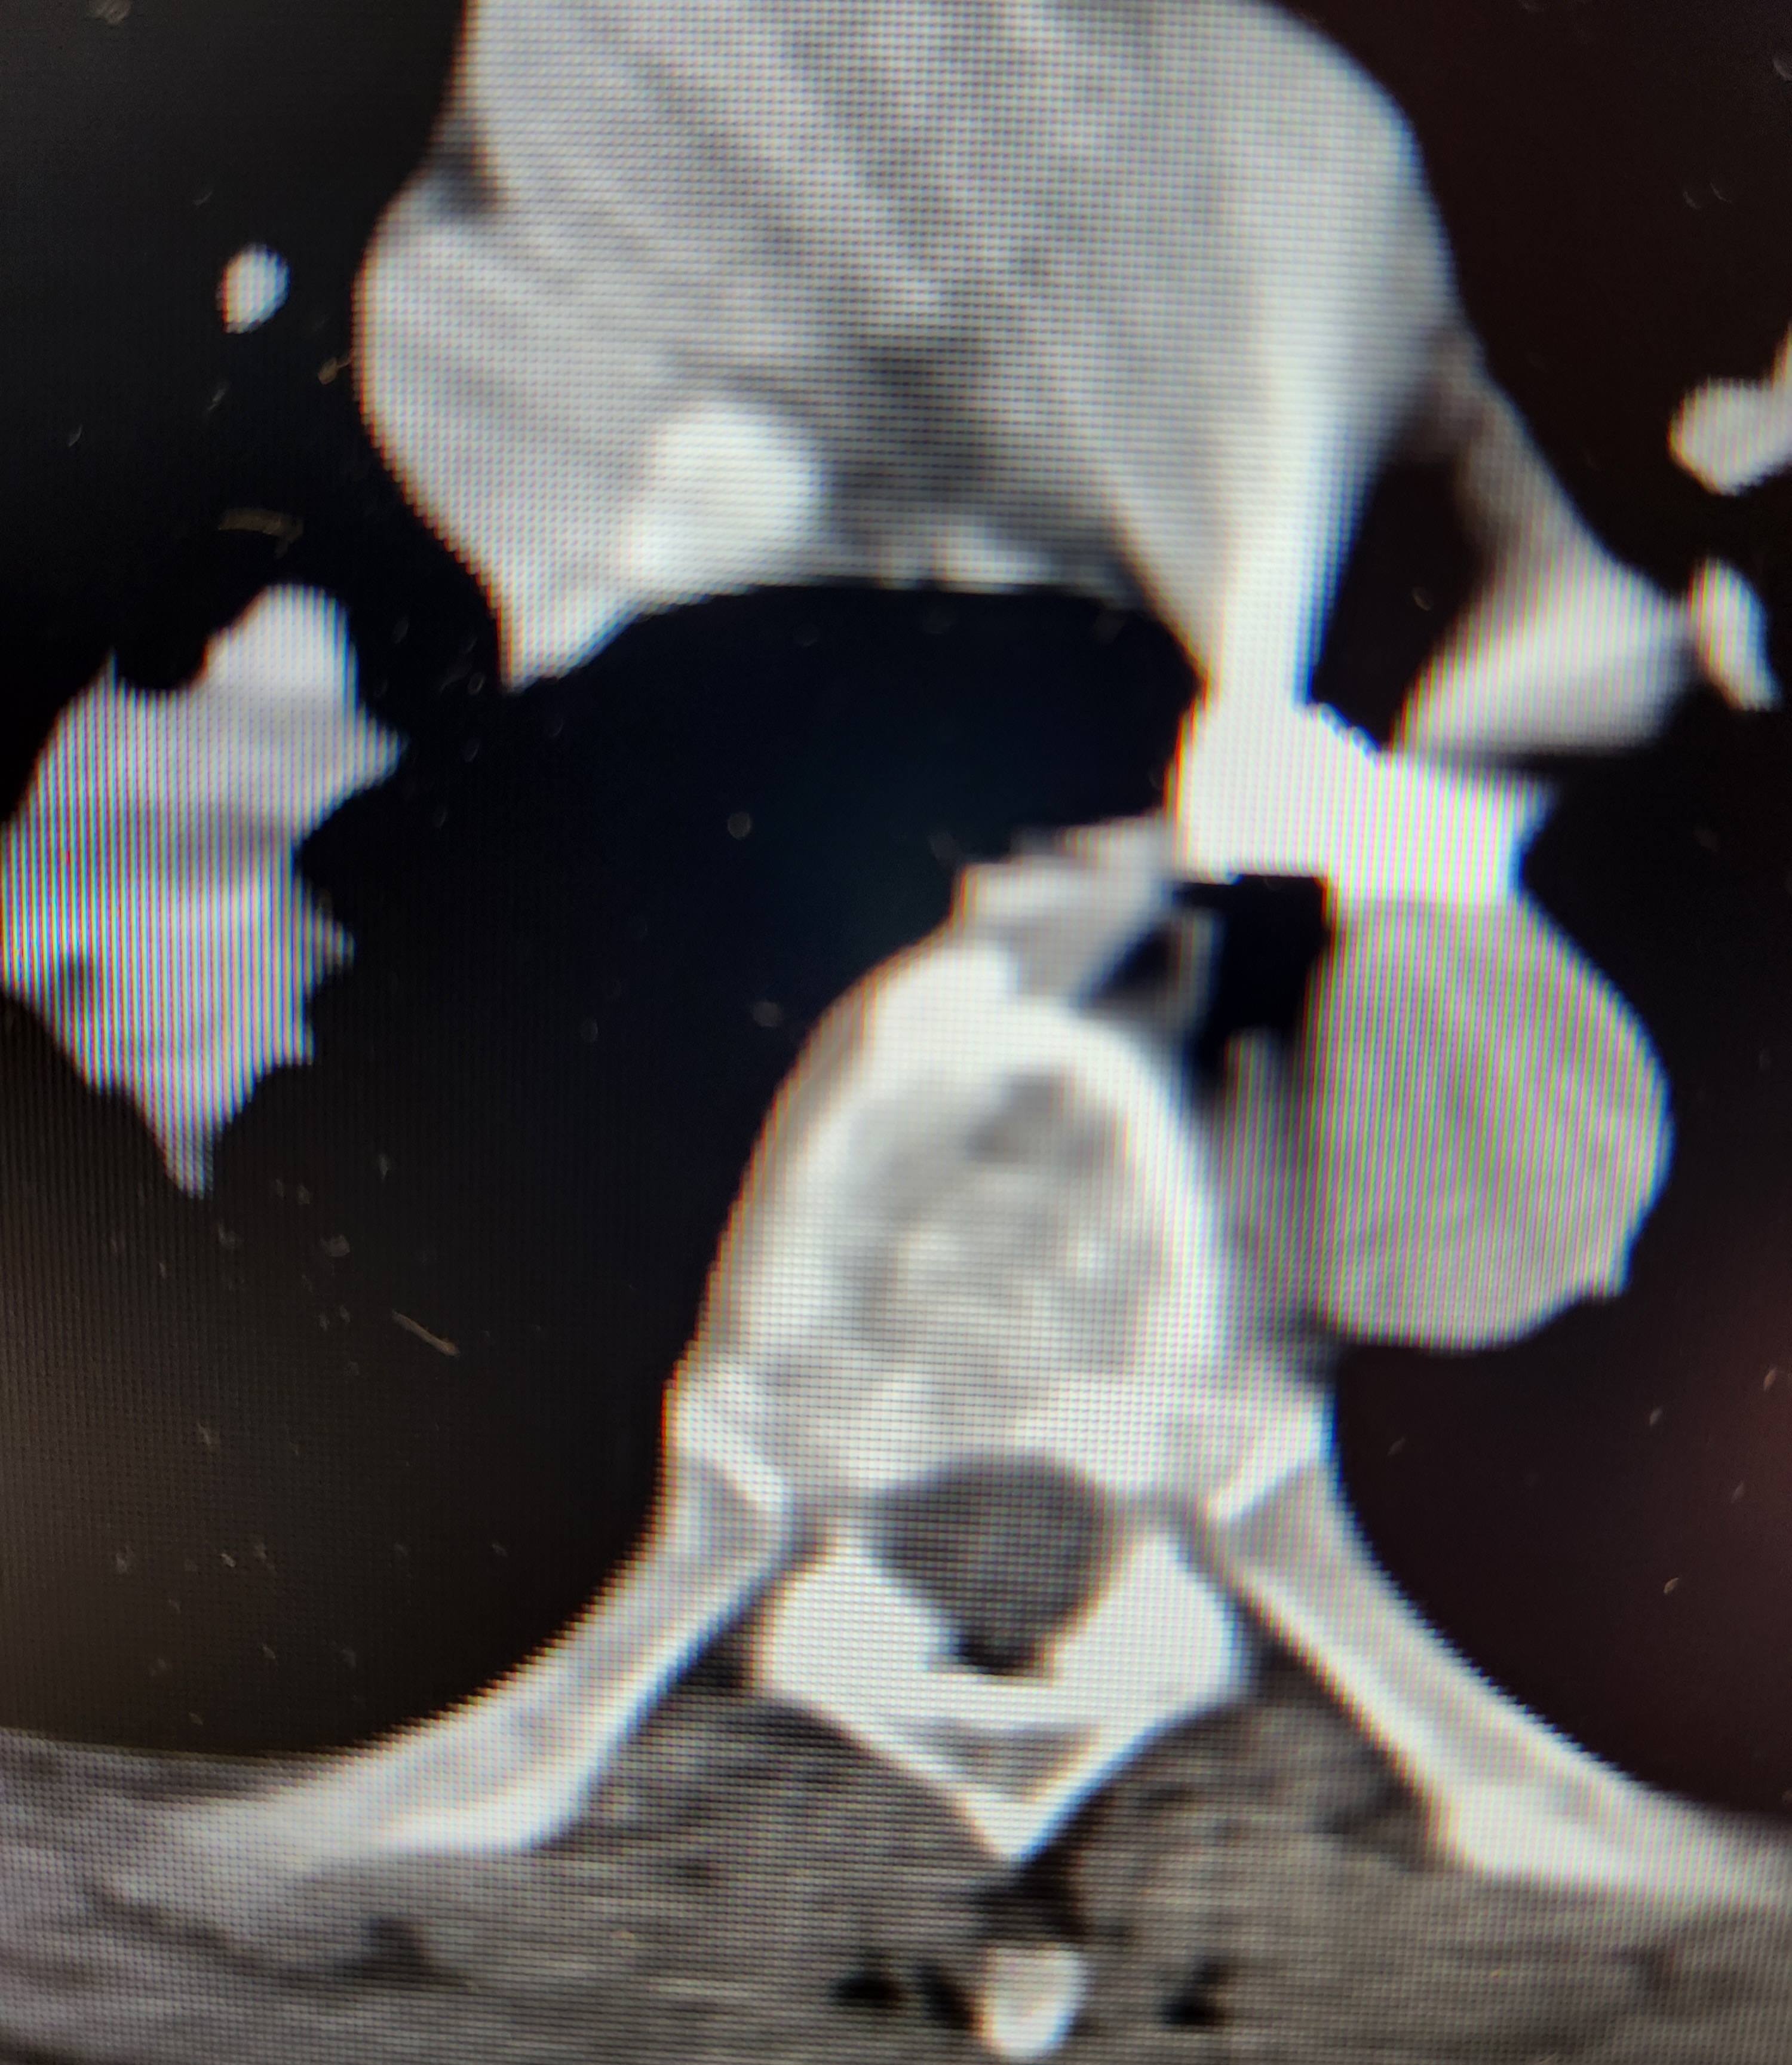

>>64449058

The expansion of hollowpoints isn't just good for preventing collateral, it also helps eliminate your target. This patient of mine, also in Detroit funny enough, got shot with what appears to be a 45acp FMJ given it's size. The bullet is literally sitting against his pulmonary and decending aortas, meaning just 1mm of expansion would have killed him. This fucker bullied our 60 year old secretary until she had to leave the desk and come to us near tears, and I regret the shooter didn't use a quality hollowpoint. Hopefully the next guy does, because with how poisonous this guy was to be around there will be a next time he gets shot in the great city of Detroit.

Here is a pic of the bullet laying against both the left pulmonary artery and decending aorta. I have now shown you the article of an event and provided photo evidence of how expansion can and does matter for lethailty. The streaking is from beam hardening artifact since the bullet is made of very dense lead, which is why we tell patients to remove jewelry and jeans (button and zipper) ect. Before their scans. It obscurs the anatomy otherwise.

Good idea.

Worth noting internal images of the body are flipped left to right, so the left pulmonary labeled is on the right side of the picture.

The pulmonary artery and decending aorta have every drop of blood in your body pumped through them in roughly 80 seconds. Pulmonaries are the path from your heart to your lungs, and once that blood is oxygenated your body pumps it through your body via the decending aorta. If pierced you bleed out and die before you could even walk from the parkinglot to the ER entrance.